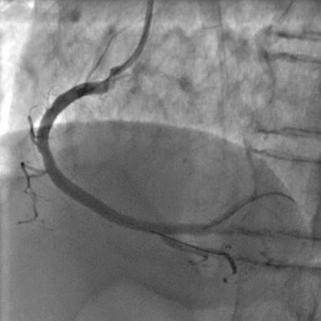

面對緊急情況,手術團隊臨危不亂,立即給予多巴胺升壓治療并快速補液。血壓很快恢復正常,造影顯示右冠遠段殘余狹窄較重,植入藥物支架后,血流恢復正常,缺血缺氧的心肌細胞得到灌注。

植入藥物支架,高壓球囊高壓后擴張后的,血流恢復,支架貼壁良好

從入院到血管再通,僅用62分鐘,比國際標準的90分鐘快了28分鐘!顯示屏上血流順暢的圖像出現(xiàn)時,醫(yī)護人員的手術衣早已被汗水浸透。術后,在醫(yī)護團隊的精心照料下,錢老伯10天后康復出院。